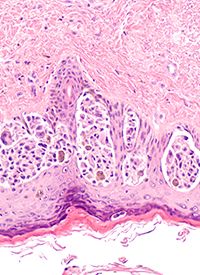

Investigators profiled human uveal melanoma metastases (n = 100) using clinicogenomics, transcriptomics, and tumor-infiltrating lymphocyte (TIL) potency assessment, and discovered that 55% of metastases had tumor reactive TILs. To better harness the TILs, study authors developed the biomarker uveal melanoma immunogenomic score (UMIS). They showed that UMIS was strongly correlated with the percentage of tumor-reactive TIL cultures (rho = +0.47; P = 7.06e−7), with reactive TIL cultures being rarely expanded among patients with a UMIS of less than 0.2.

Additional findings from the study revealed that UMIS high metastases had more lymphoid cells (proportion ratio = 10.50, P = .047) and fewer tumor cells (proportion ratio = 0.88, P = .047) compared with UMIS low metastases. Additionally, study authors noted that the TIL in the UMIS high metastases had “undergone activation and effector differentiation consistent with an in vivo adaptive anti-tumor response and indicative of a T cell-inflamed microenvironment.”